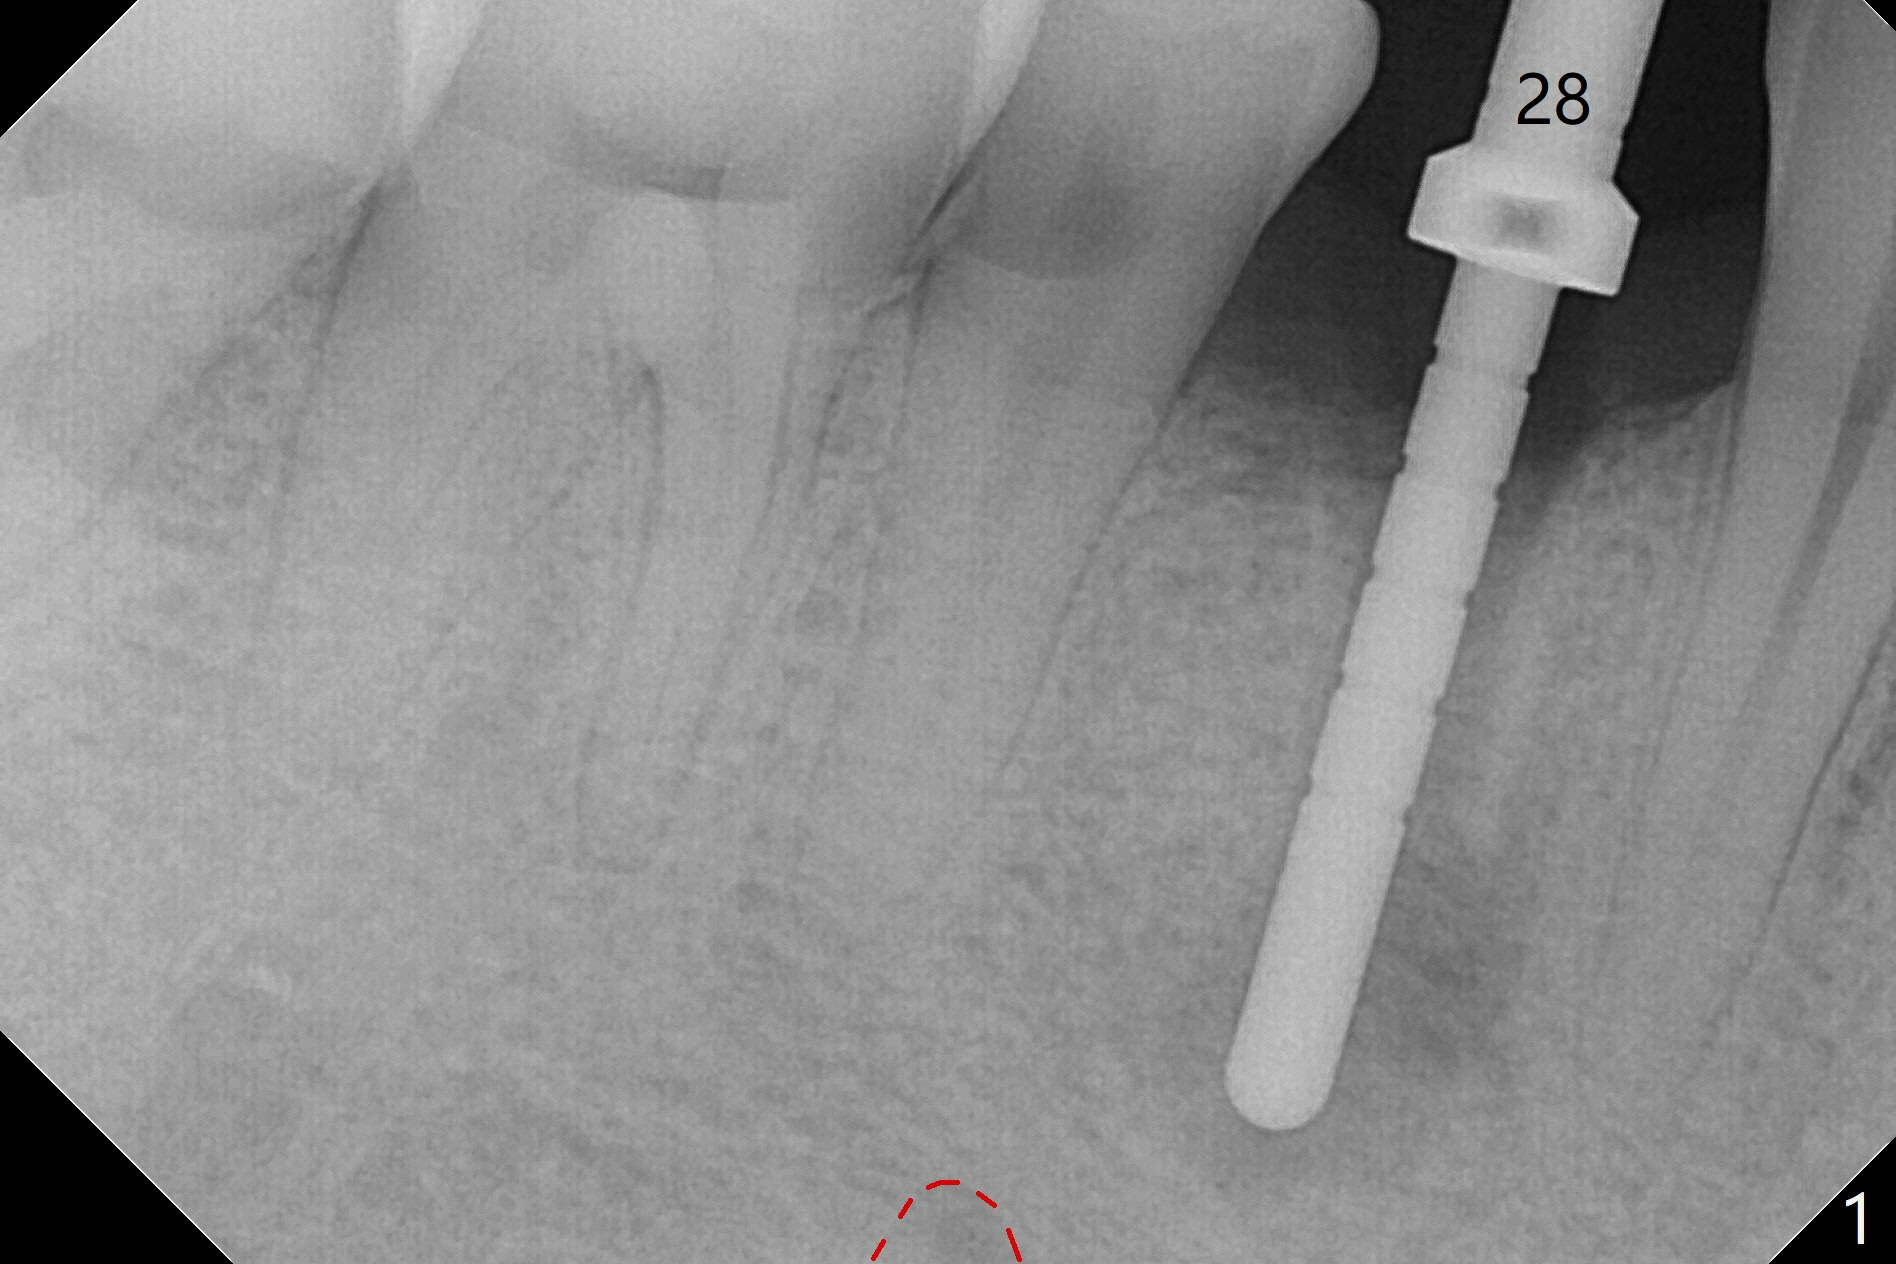

Immediately post extraction and curettage of the large buccal apical lesion, osteotomy is established in the lingual wall of the socket of #28 (slightly distal) for 17 mm vs. 15 mm socket depth (Fig.1 (red line: Mental Loop)). Following sequential osteotomy until 3.5x17 mm drill, a 4x10 mm dummy implant is partially placed with stability (Fig.2,3 (root measurement: mesiodistal 4 mm; buccolingual 7 mm)). A final implant (4x11.5 mm) is placed with insertion torque of 60 Ncm (Fig.4,5). Since the buccal crest is lower with the buccal gingival recession, the implant is intentionally placed deep as well as lingually so that autogenous bone and Vera graft mixture will be placed in the buccal gap (Fig.6 * (gauze at the moment)). The apical lesion decreases 4.5 months postop (Fig.7). Immediate implant and immediate provisional keep the papillae (Fig.8 *), but cannot prevent the buccal plate from atrophy (Fig.9 *). It appears that socket shield is able to accomplish the latter. The bone density next to the coronal threads increases 10 months post cementation (Fig.10 *) and seems to have continued to do so 1 year 4 months post cementation (Fig.11).